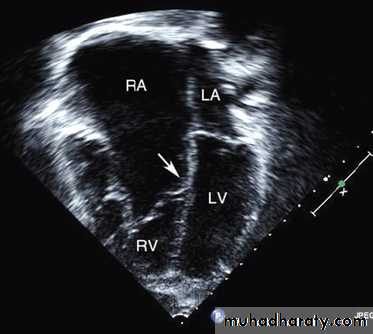

Ebstein anomaly consists of downward displacement of an abnormal tricuspid valve into the right ventricle.

The right ventricle is divided into 2 parts by the abnormal tricuspid valve: the 1st, a thin-walled “atrialized” portion, is continuous with the cavity of the right atrium; the 2nd, often smaller portion consists of normal ventricular myocardium.

RV output is decreased due to a combination of the poorly

functioning small right ventricle and tricuspid valve regurgitation,

Echo is diagnostic and shows the abnormalities.